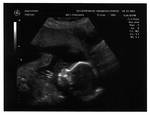

Gallery :: 2005 :: Ultrasound